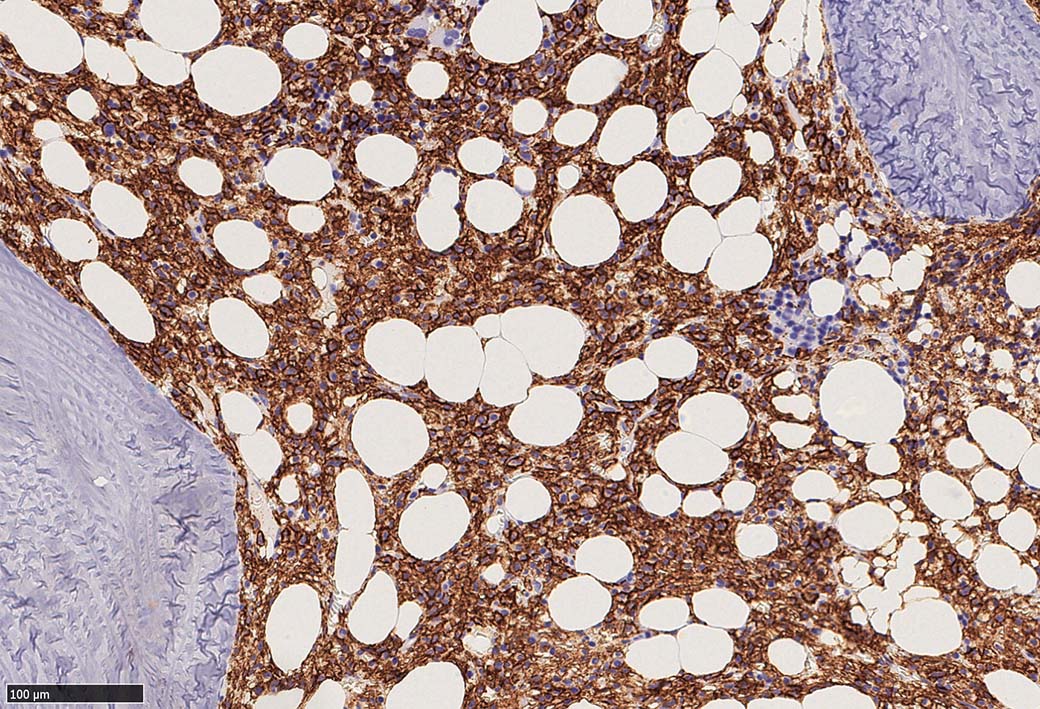

増殖細胞はCD20(相変わらずべったり染まる), CD19, PAX5陽性 CD25陽性.

BRAF V600E変異タンパクの免疫染色(山梨医大 大石先生に染色していただきました. ベンタナ, Optiview)

Pathological Diagnosis: Hariy cell leukaemia